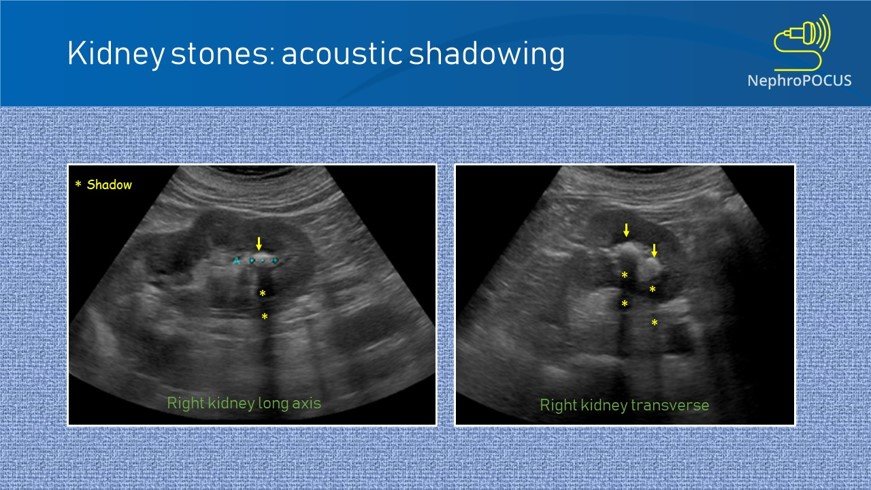

The bright echogenic focus marked by the arrow represents a renal calculus.

Behind this echogenic focus, there is a posterior acoustic shadow (dark vertical band), which is a key diagnostic feature of a stone.

Left renal stone is seen as an echogenic focus with posterior acoustic shadowing. No dilatation of the renal cavities.